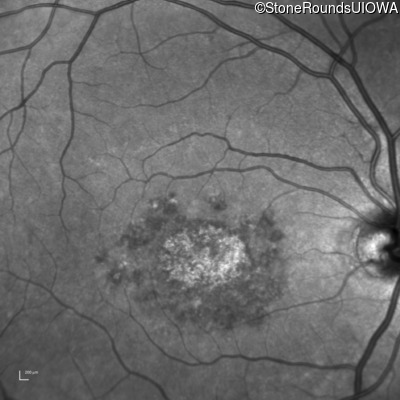

Blue Autofluorescence - Right - 20/200 -2 sc

Exemplar